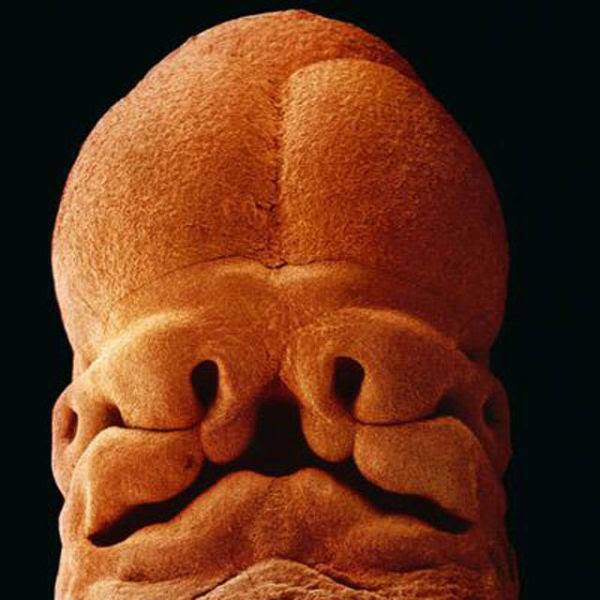

8.胚胎開始發育腦部,這時候胚胎的形狀看起來真的好奇特,完全想不到它竟然會進化成寶寶啊!

9.懷孕24天, 胚胎還沒有發育出任何骨骼,只有一顆從受孕第18天起就開始跳動的心臟。